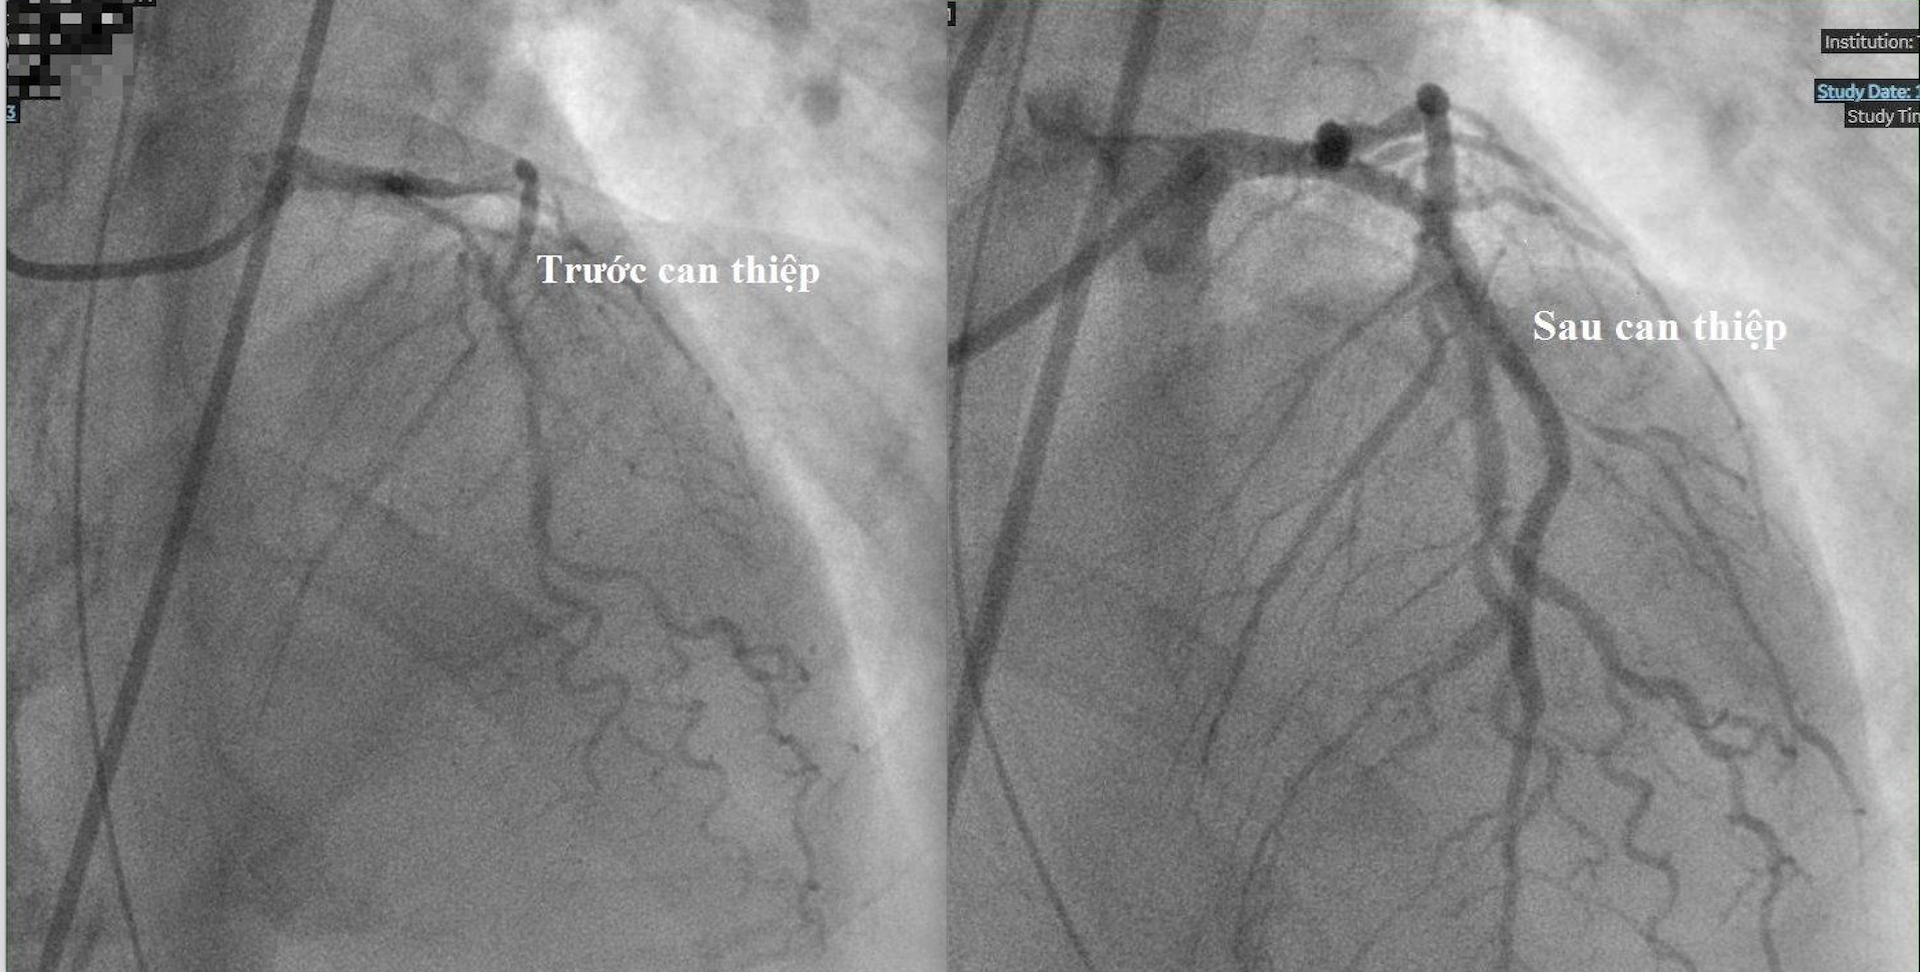

Qua hội chẩn toàn viện, các bác sĩ chẩn đoán ông S. bị nhồi máu cơ tim cấp. Kết quả chụp mạch vành cho thấy người bệnh bị tắc động mạch lớn nhất nuôi tim, 2 nhánh còn lại bị hẹp. Ca can thiệp đặt 2 stent mạch vành cho người bệnh diễn ra suôn sẻ vào chiều cùng ngày.

Bệnh nhân nhồi máu cơ tim cấp được đặt 2 stent tại Bệnh viện Trưng Vương. Ảnh: BVCC.